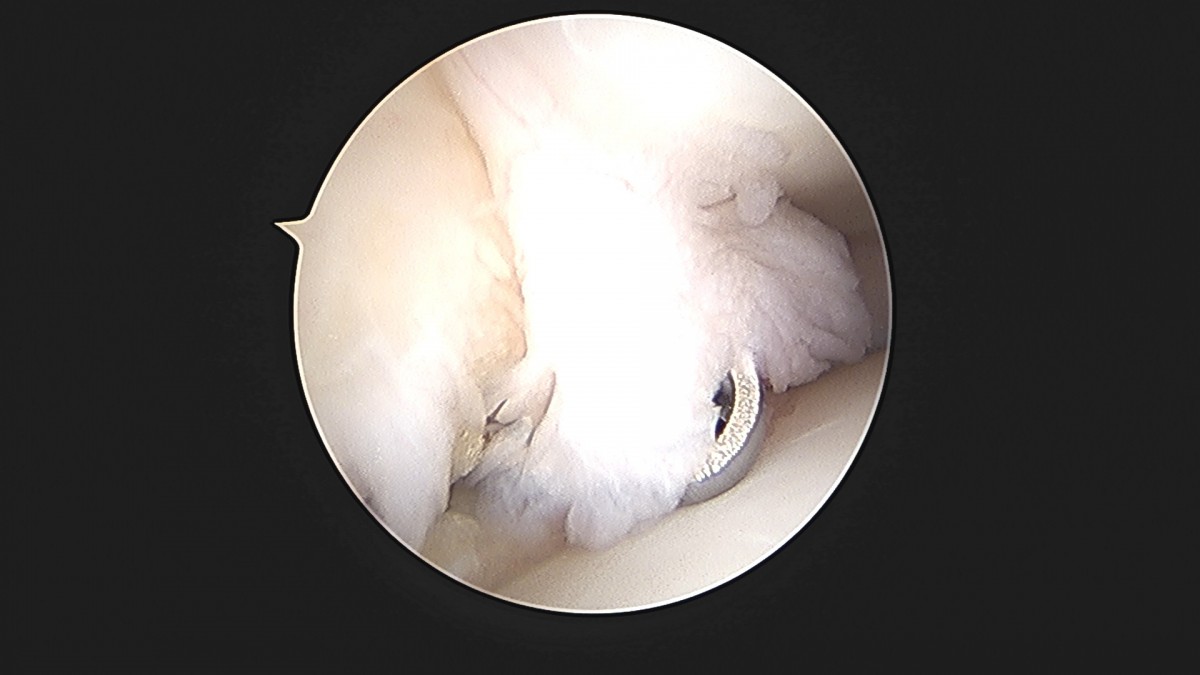

이재상원장님 발목 활액막 절제술 및 인대 봉합술 이승O 환자

작성자 최고관리자 댓글 0건 조회 787회 작성일 25-09-16 15:24